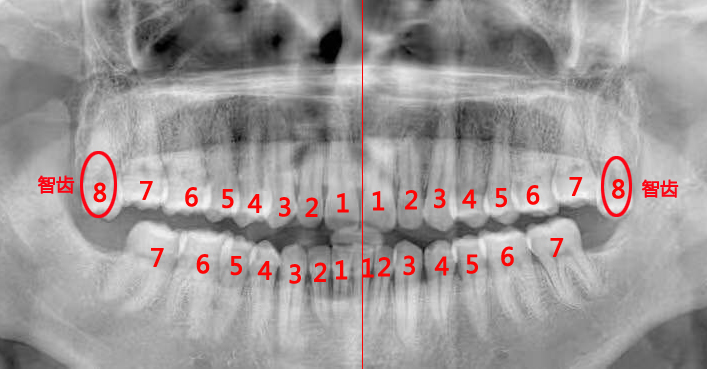

最准确的方法:拍片检查,借助X光让智齿现形。

说明:检查智齿或拔智齿前,医生一般都会建议拍个全景片,很多人觉得麻烦,其实这是非常有必要的。全景片可以清晰地呈现上下颌骨、全口牙列的全貌,以及智齿与邻牙、周围牙槽骨的关系,帮助医生评估拔牙的难度,并安全快速地拔除智齿。拍片时,需要穿防护服。

图:全景X光牙片机